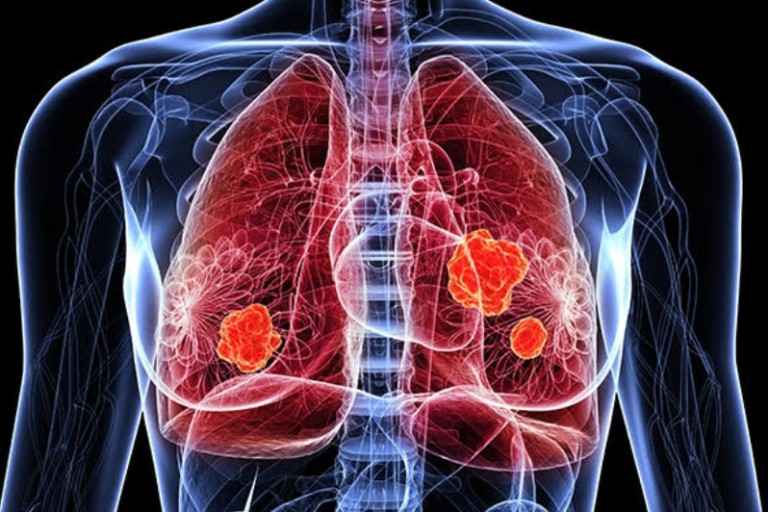

폐암은 위암, 갑상선암 다음으로 3번째로 발병 빈도가 높은 3대 암 중 한 가지인데요. 폐암은 재발과 전이까지의 빈도도 잦은지라 완치가 어렵다고 하며 폐암 발병 초기에는 거의 증상이 없을 수가 있어 수술이 불가능한 3기, 혹은 4기에 주로 진단된다고 해요.

폐암 초기증상 폐암 4기에 이르게 되면 5년 생존률이 30% 대로 감소하게 된다고 해요. 그리하여 폐암은 암 질병이자 중 사망자 비율이 가장 높은 것으로 나타나고 있어요.

폐암은 사망률 2위를 차지하고 있는 간암에 비해 무려 2배에 가까운 사망률을 보이고 있다고 합니다. 이렇게 치명적인 폐암에 대해 미리 알고 대처하는 것이 바람직할 것 같아요. 아래에서는 폐암이라 판단해 볼 수 있는 그 초기증상에 대해 간단히 설명드릴게요.